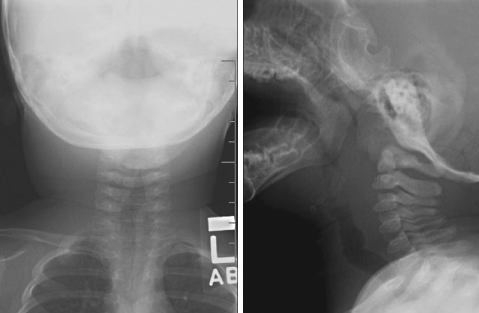

<p>A 5-month-old girl is brought for evaluation of a neck swelling that had appeared 2 days earlier and had pro- gressively enlarged. She has also had cough and subjective fever. She has had no...